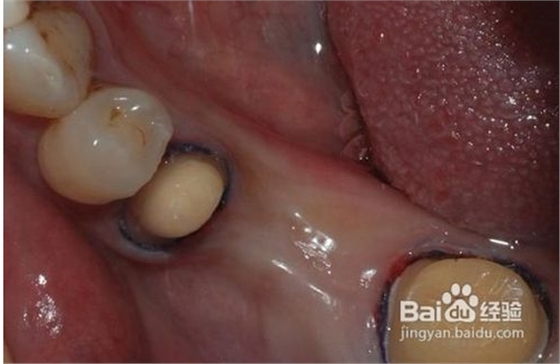

1、磨牙

為了使完成后的烤瓷牙冠戴入后不超過(guò)原始狀態(tài)的外牙厚度,一般做烤瓷牙要磨除部分自然牙。另外為了使假牙順利就位并獲得良好的固位,要將基牙制備成一定的形狀?;乐苽涞暮脡模P(guān)系到假牙是否容易戴入以及牢固性。

4、試戴粘接

大約1周后制作的烤瓷牙即可完成。首先經(jīng)過(guò)試戴,檢查肩臺(tái)的密貼性,即冠邊緣適合性要符合標(biāo)準(zhǔn),顏色是否一致,形態(tài)是否美觀,以及鄰接關(guān)系,咬合關(guān)系等。如果確認(rèn)沒(méi)有問(wèn)題,醫(yī)生通過(guò)特殊粘接劑,粘接在預(yù)修復(fù)的牙體上,烤瓷牙的修復(fù)工作全部

完成。